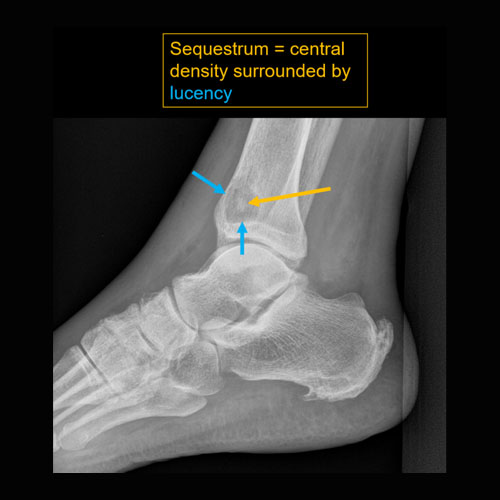

There is cloaca, sequestrum, or involucrum. |